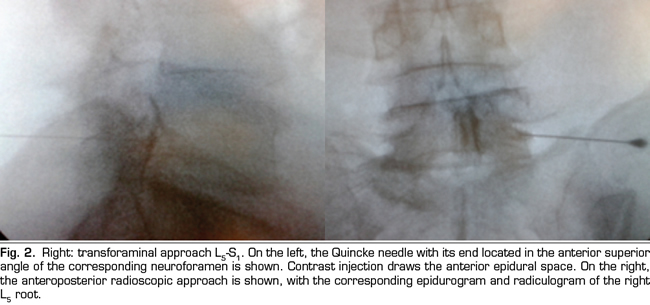

Figure 1